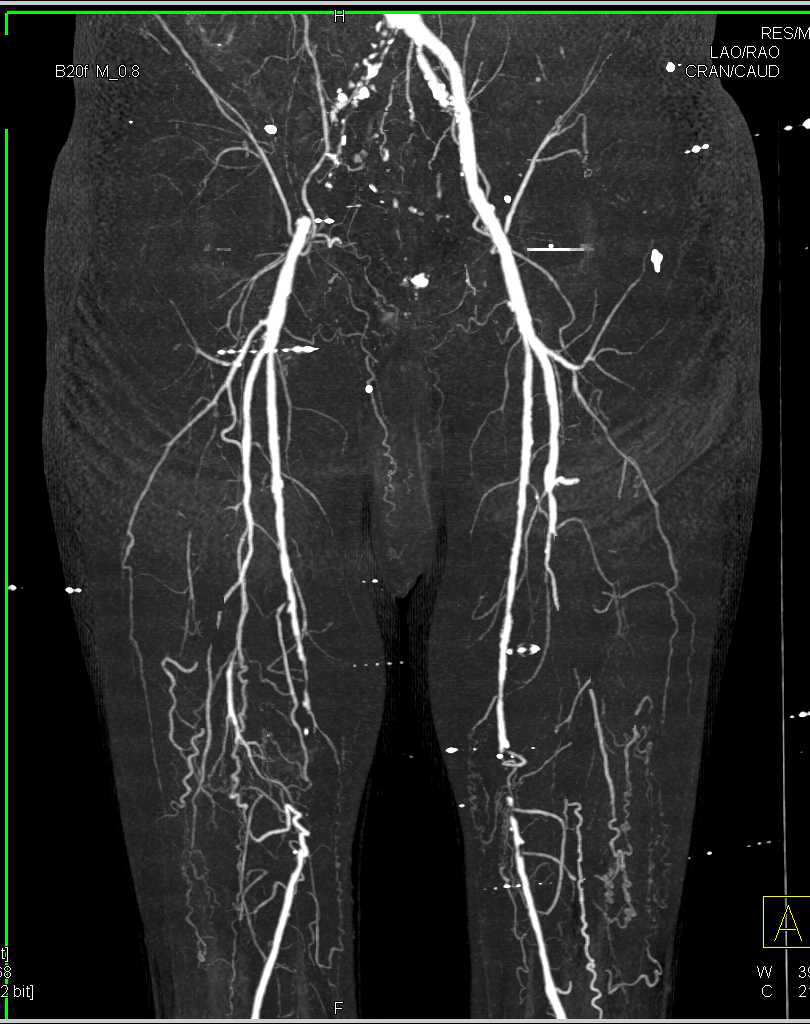

Celiac Stenosis and Superior Mesenteric Artery (SMA) Occlusion